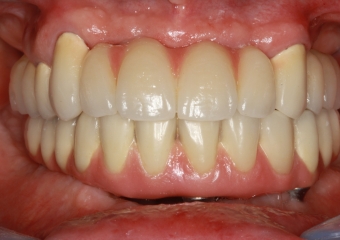

Próteses fixas em porcelana superior e inferior sobre implantes Cone Morse

Sorriso final do caso terminado em 2012